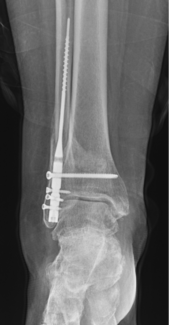

05/01/2025

Nevin Joseph, DPM; Ian Barron, DPM, FACFAS; Timothy Holmes, DPM, FACFAS

Patients are living longer, and meaningful management of ankle fractures in older patients warrants closer examination. Here, these authors present important insights on these injuries, including what the current literature reveals.

Podiatry Today